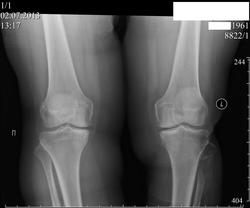

Пациентка 52 лет.Жалобы на боли в коленных суствах, больше справа, ноющие , усиливающиеся при движении. Можно ли не зная анамнеза определиться, что же было с  малоберцовой костью

Операций не было. Была травма голени, с углообразным переломом малоберцовой кости в верхней трети в 2008году (так написано в протоколе R-исследования коленного сустава). Я предполагаю, что сейчас мы видим результат неправильно лечённого перелома малоберцовой кости и не зная анамнеза разобраться в этом, практически не представлятеся возможным.Хотя Dima  и Андрей Юрьевич показали  свою сверхпрницательностьyes! Я то же, пока не прочитал запись в амбулаторной карте, предполагал , что вероятно была какая-то резекция кости.

yes! Кстати, у пациентки после травмы (автоаварии) развилась нейропатия малоберцового нерва!

Малоберцовая кость у человека не несёт осевой нагрузки. С её сращением не бывает проблем при изолированных переломах в верхней трети, даже если их совсем не иммобилизировать. Ну, вспомните хоть один случай несращения. А здесь то ли дефект, то ли атрофический ложный сустав, называйте как хотите. Откуда ему взяться без остеомиелита? Может неврит малоберцового нерва поспособствовал? Но если в карточке так написано, значит правда. Или всё таки был перелом большеберцовой кости в нижней трети, который остался за кадром?

Да, коллега вы правы.Насколко я понял было серьёзное ДТП:   последствием которого явился перелом костей голени( авария была в 2004 году); при чём при описании R-граммы коленного сустава от 2008г.отмечено, что имеет место углообразный перелом верхней трети малоберцовой кости.